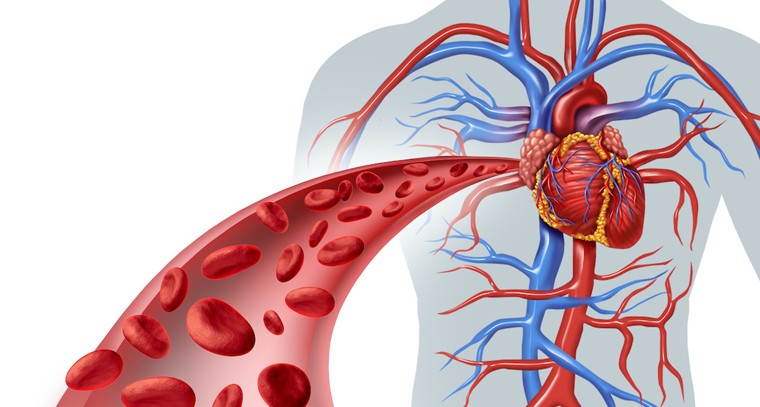

రక్త ప్రసరణ మెరుగవ్వాలంటే చేయండిలా